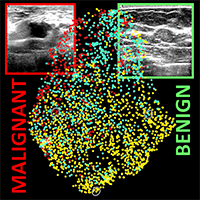

Characteristics of tumors that can remain hidden in medical images are being tested for the ability to predict risk, prognosis and response to cancer therapy. This approach is part of a powerful emerging field in medical physics called radiomics, which seeks to extract statistical information from images to make better treatment decisions. Radiomics research also helps determine how information from medical images can be combined with genomic information from individual patients to improve outcomes. A special session on Monday presents the fundamentals and latest advances in combining quantitative imaging and genomics in the practice of medical physics.

Characteristics of tumors that can remain hidden in medical images are being tested for the ability to predict risk, prognosis and response to cancer therapy. This approach is part of a powerful emerging field in medical physics called radiomics, which seeks to extract statistical information from images to make better treatment decisions. Radiomics research also helps determine how information from medical images can be combined with genomic information from individual patients to improve outcomes. A special session on Monday presents the fundamentals and latest advances in combining quantitative imaging and genomics in the practice of medical physics.